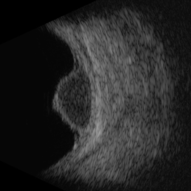

Orange Pigment Overlying a Lesion Suspicious for a Choroidal Melanoma

Orange Pigment Overlying a Lesion Suspicious for a Choroidal Melanoma

Jan 16 2019 by John S. King, MD

76-year-old white male saw his eye doctor with a three week complaint of photopsias and a shadow in his vision. Found to have a 10.5/12.5/2.5 (medium reflectivity) pigmented, choroidal mass associated with SRF and orange pigment (hyper-autofluorescence of lipofuscin), and without drusen or halo. See photo

Photographer: Stacey Coleman

Imaging device: Topcon 50

Condition/keywords: lipofuscin, orange pigment